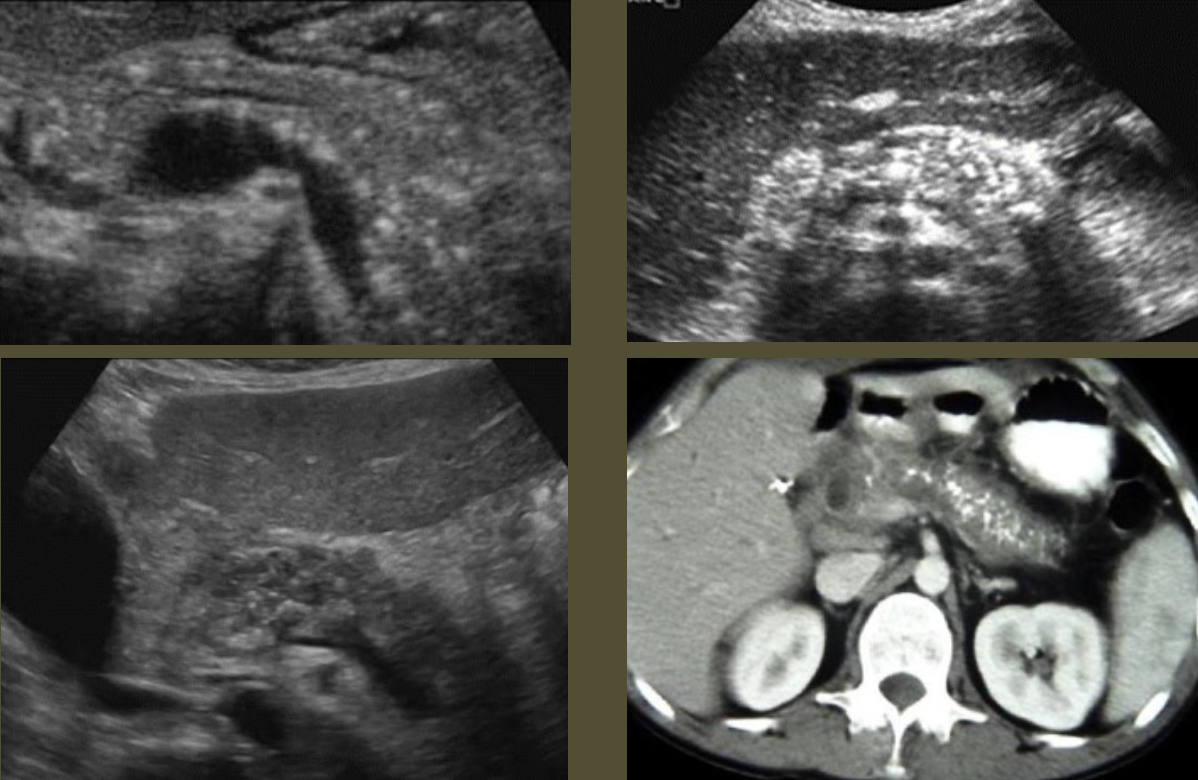

AAA (Abdominal Aortic Aneurysm) → focal dilation of aorta

2D US presentation: focally dilated AO (3 cm or greater), mural hypoechoic thrombus, wall calcifications, usually located infrarenal, can be fusiform or saccular

color doppler: turbulent helical flow

DDX: aortic dissection (aorta may be enlarged, but has intimal flap), pseudoaneurysm (focal outpouching w/ narrow neck, but not all 3 layers involved)

Pseudoaneurysm → rupture from intima layer contained in deeper layers of artery wall

2D US presentation: heterogenous, pulsating central structure with internal swirling of brighter echogenicity

color doppler: “yin-yang” sign, “to and fro” PW waveform

DDX: hematoma (hypoechoic intraluminal echoes, but not color flow or neck connecting), true aneurysm (wide rather than narrow neck continuous w/ artery, chronic rather than acute)